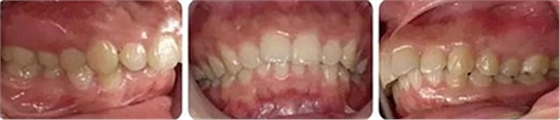

女性,24歲,主訴牙列不齊,面型突。

開(kāi)唇露齒,閉口時(shí)唇肌緊張,反笑線(xiàn),突面型。

上下牙列輕度擁擠,牙弓偏尖圓形;前牙深覆合深覆蓋;雙側(cè)磨牙尖牙偏遠(yuǎn)中關(guān)系。